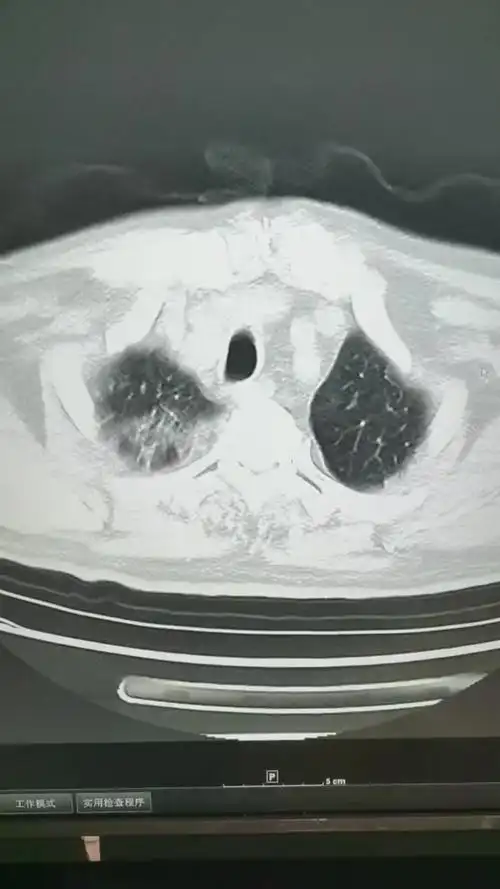

和大家认识一下这就是新冠大白肺的样子病毒性肺炎